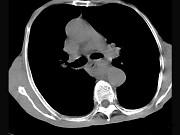

问题 女,71岁,进食时有梗阻感,进行性加重半年,影像检查如图,最可能的诊断是()

选项 A.贲门失弛缓症 B.食道癌并纵隔淋巴结转移 C.食道良性狭窄 D.返流性食道炎 E.食道静脉曲张

答案 B